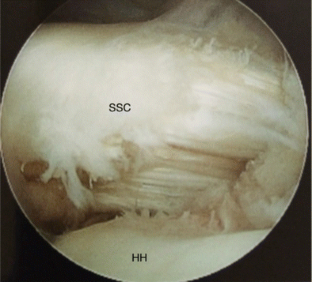

Fig. 3